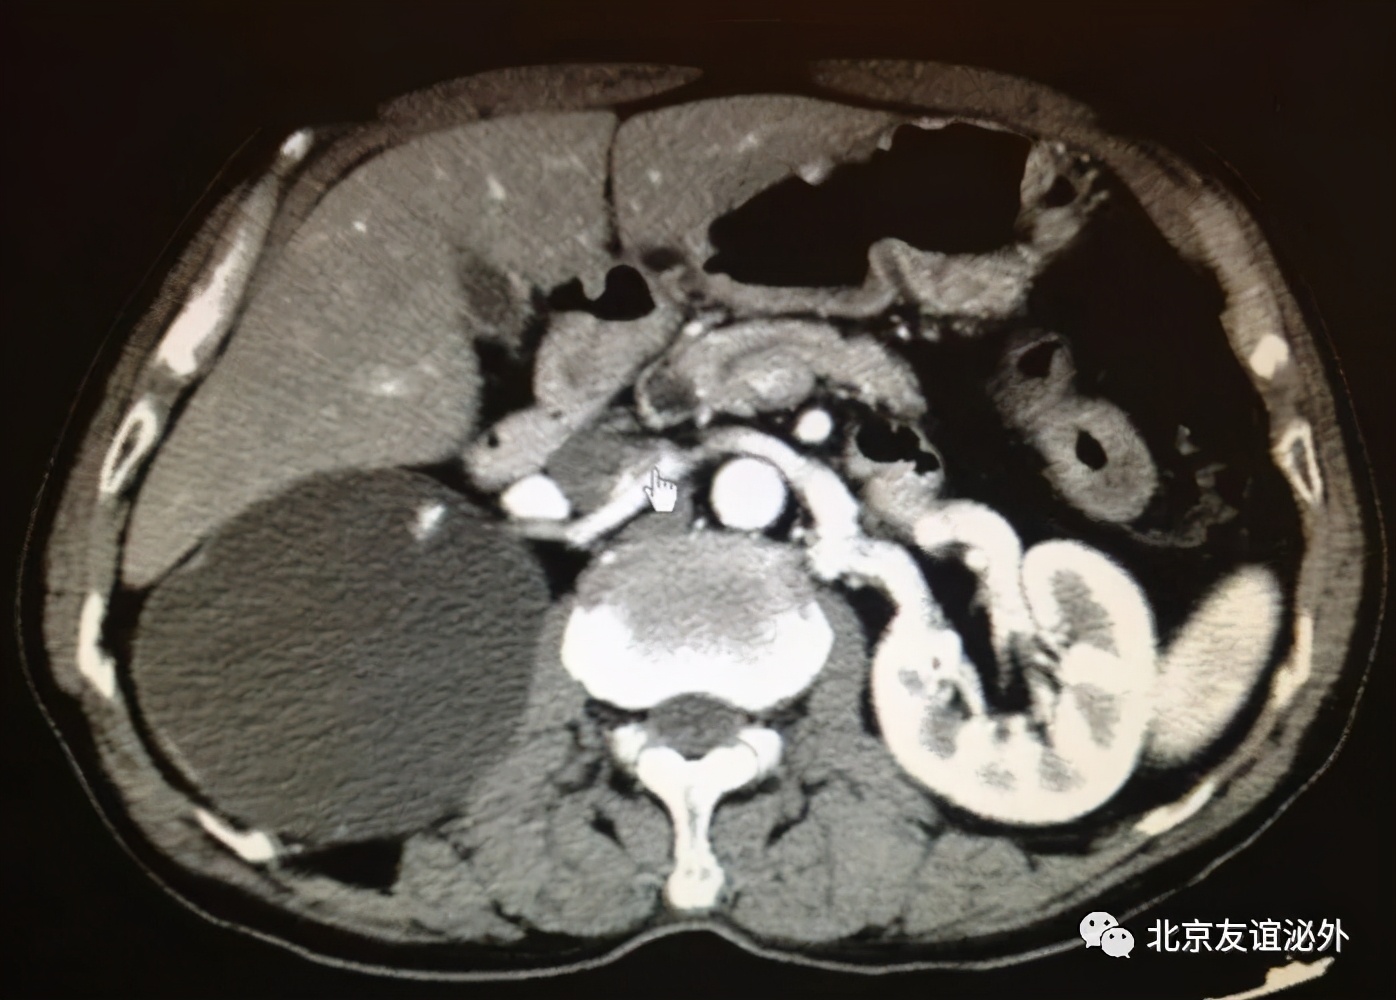

图2. Bosniak I级恶性囊肿(肾透明细胞癌),临床极为少见